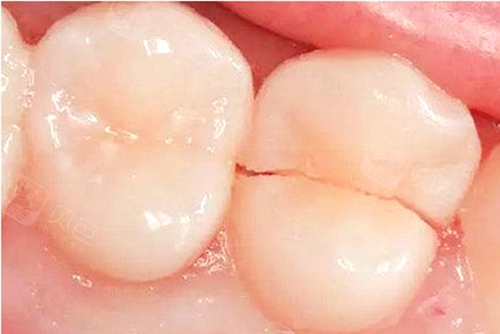

牙隐裂、牙齿非龋性破坏疾病

牙齿牙尖过尖、咬合过紧、牙齿发育不良等可导致牙齿出现裂纹,另外有的人习惯长期咀嚼硬物,甚至牙齿开啤酒盖等习惯,也可导致牙齿隐裂或缺损,严重的牙齿隐裂或缺损可致牙齿劈开且无法保留,导致缺牙。牙齿磨耗和楔状缺损也是导致老年人牙体和牙列缺损的主要原因。

因此,为了预防该类疾病导致缺牙,除了需要破除不良习惯外,更重要的是要养成定期检查牙齿的习惯,以便早发现早治疗。

隐裂的牙齿从中间劈裂开导致患牙无法保留